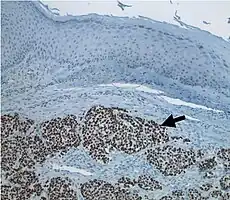

Diagnosis of MCC begins with a clinical examination of the skin and lymph nodes.[25] Following clinical exam, definitive diagnosis of Merkel cell carcinoma (MCC) requires examination of biopsy tissue to identify its histopathologic features.[3][25] An ideal biopsy specimen is either a punch biopsy or a full-thickness incisional biopsy of the skin including full-thickness dermis and subcutaneous fat. On light microscopy, MCC shows basaloid tumor nests with neuroendocrine features ("salt and pepper" chromatin, scarce cytoplasm, and brisk mitotic activity).[3][25] In addition to standard examination under light microscopy, immunohistochemistry (IHC) is also generally required to differentiate MCC from other morphologically similar tumors such as small cell lung cancer, the small cell variant of melanoma, various cutaneous leukemic/lymphoid neoplasms, and Ewing's sarcoma. Neuroendocrine molecular markers such as synaptophysin or chromogranin A are characteristic of MCC and other neuroendocrine tumors, while other markers such as PAX5 or cytokeratin 20 can distinguish MCC from these tumors.ref name=Kervarrec2019/>[4] Longitudinal imaging may also help in ruling out a diagnosis of metastatic small cell lung cancer. Once an MCC diagnosis is made, a sentinel lymph node biopsy as well as other imaging is recommended as a part of the staging work-up needed to determine prognosis and subsequent treatment options.[3][25]

Merkel-cell carcinoma. Gross pathology specimen Micrograph of a Merkel-cell carcinoma. H&E stain

Micrograph of a Merkel-cell carcinoma. H&E stain Merkel-cell carcinoma (arrow) infiltrating skin tissue, stained brown for Merkel cell polyomavirus large T protein

Merkel-cell carcinoma (arrow) infiltrating skin tissue, stained brown for Merkel cell polyomavirus large T protein